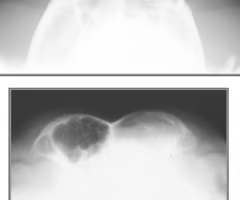

What view is this and what is the pathology?

Oblique - tooth route abscess

Is the yellow arrow a pathology?

No- common in young horses w/ teeth still growing

What is the pink structure?

Dental cap/ baby tooth

What is the purple structure?

Adult tooth